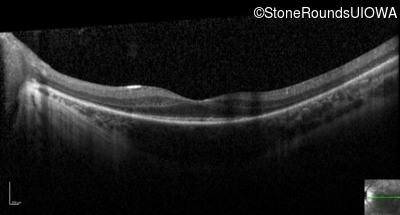

Optical Coherence Tomography - Right - 20/60

Exemplar / OCT Stack